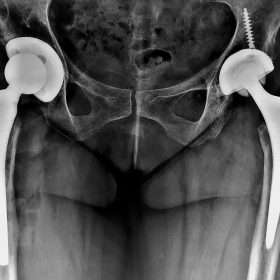

Παραδοσιακά οι αρθροπλαστικές ισχίου αποτελούνται από μια μεταλλική μπάλα – σφαίρα τοποθετημένη σε μια πλαστική κοιλότητα (κοτυλιαία πρόθεση).

Η πλαστική επιφάνεια στήριξης φθείρεται με την πάροδο του χρόνο, με ρυθμό μάλλον σχετιζόμενο με το επίπεδο δραστηριότητας του ατόμου. Αυτό έχει σαν επακόλουθο νεότεροι ασθενείς με μεγαλύτερο προσδόκιμο ζωής να έχουν αυξημένο ρίσκο αναγκαιότητας δεύτερης αρθροπλαστικής ισχίου (αναθεώρησης – Revision) επέμβαση που είναι πολυπλοκότερη και υπόκεινται σε υψηλότερο κίνδυνο επιπλοκών. Βάση των ανωτέρω, ιστορικά, η αρθροπλαστική ισχίου σπανίως εφαρμοζόταν σε ασθενείς κάτω των 60 ετών.

Χάρη στα νέα τεχνολογικά επιτεύγματα έχουν παραχθεί επιφάνειες στήριξης που ανταποκρίνονται σε μεγαλύτερα επίπεδα δραστηριότητας και αναμένεται να έχουν μεγαλύτερη διάρκεια ζωής. Αυτές οι καινούριες επιφάνειες στήριξης είναι συνήθως μέταλλο πάνω σε ειδικό σκληρότερο πλαστικό ή κεραμικό πάνω σε κεραμικό. Ως εκ τούτου, είναι τώρα πολύ πιο σύνηθες, νεότεροι ασθενείς να χειρουργούνται καθώς η πλειονότητα αυτών, που η αρθρίτιδα τους προκαλεί αφόρητους πόνους, επιλέγουν να έχουν ποιότητα ζωής από το να ζουν με τον πόνο.

Η αρθροπλαστική ισχίου αποτελεί μια αποτελεσματική επέμβαση αποκατάστασης και πρέπει να εφαρμόζεται μόνο όταν οι ασθενείς δεν είναι σε θέση να αντέξουν άλλο τον πόνο και την ανικανότητα και εφόσον τα πλεονεκτήματα καθώς και οι πιθανοί κίνδυνοι της μεθόδου έχουν εξηγηθεί πλήρως από το χειρουργό και έχουν κατανοηθεί από τον ασθενή.